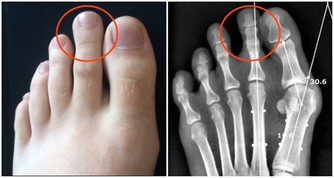

真菌感染:有毛癬菌所致的股癬、甲癬、足癬和手癬;有念珠球菌所致的口炎、陰道炎、巴氏腺炎,同樣也是好好壞壞難以根治。

糖尿病足:高血糖導致下肢血管、神經系統病變,一旦皮膚稍有破損、感染而不及時感知或治療,將會迅速形成潰瘍、壞疽,最終不得不做截肢處理,造成病人身體上、心理上雙重打擊,生活質量大大下降,嚴重的甚至還會危及生命。